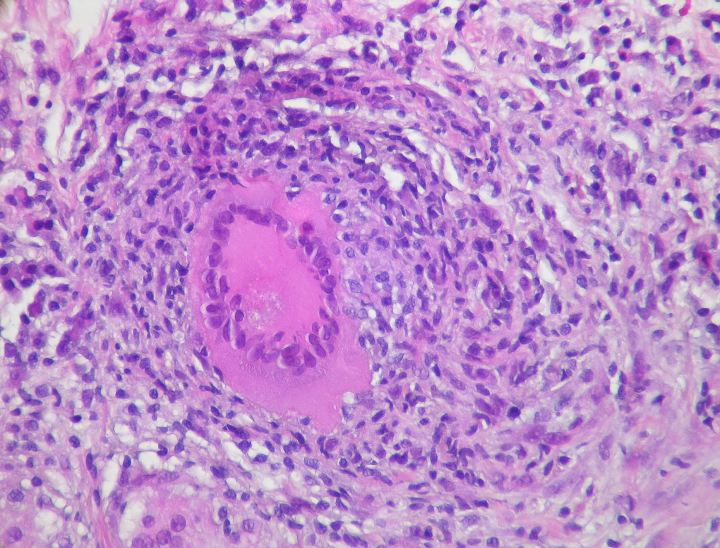

Although the dangers of tuberculosis (TB) are widely known, many people do not know that a large percent of tuberculosis patients are also HIV positive. This issue is especially prevalent in Africa, Ethiopia specifically, where TB has been a large public health issue for over fifty years. This large health epidemic prompted Mulugeta Dalbo of the Arba Minch Health Science College in Arba Minch, Ethiopia to perform a retrospective follow-up study in order to analyze the high incidence of HIV/TB cases.

The study, conducted at the Arba Minch General Hospital, included 496 HIV positive patients with a mean age of 33.8. The study looked at behavioral habits, clinical characteristics, and socio-demographic status of the participants. They determined that the incidence rate of TB among the patients was 21.4%. Through bi-variable logistic regression, it was concluded that factors such as age, sex, history of cigarette smoking, hemoglobin level, and family size were predictors of TB, while education and marital status were not. Since smokers were three times more likely to develop TB than non-smokers, this study reveals a large need to fight smoking within the HIV community. The results of this study show the need to make lifestyle changes in order to help combat the TB/HIV problem in Ethiopia.